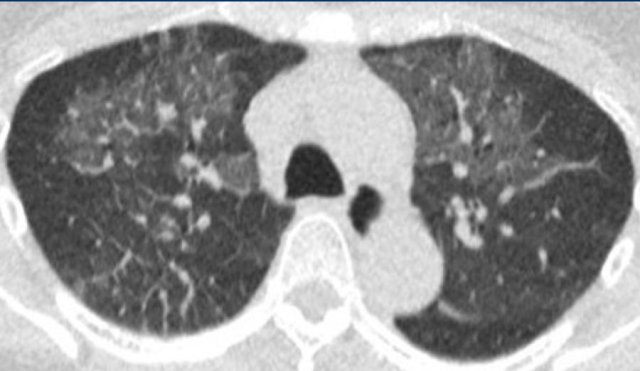

Bilateral and confluent airspace opacities caused by diffuse alveolar hemorrhage such as in e.g. systemic lupus erythomathosus on this image are distributed more along the bronchovascular bundles, and predominantly spare the peripheral pleural surfaces and costophrenic angles.

These opacities should resolve in weeks if bleeding does not recur.

The image shows alveloar hemorrhage with patchy groundglass along the bronchovascular bundles in a patient with secondary vasculitis in systemic lupus erythemathosus.

In COVID-19 the groundglass is more peripheral and diffuse.

More chronic or subacute hemorrhage causes crazy paving and fibrosis.

In addition, clinical presentation including fever, cough and leukocytosis are less common in patients with alveolar hemorrhage, although the clinical presentation of diffuse pulmonary hemorrhage remains highly variable.

Only approximately 2/3 of patients have hemoptysis